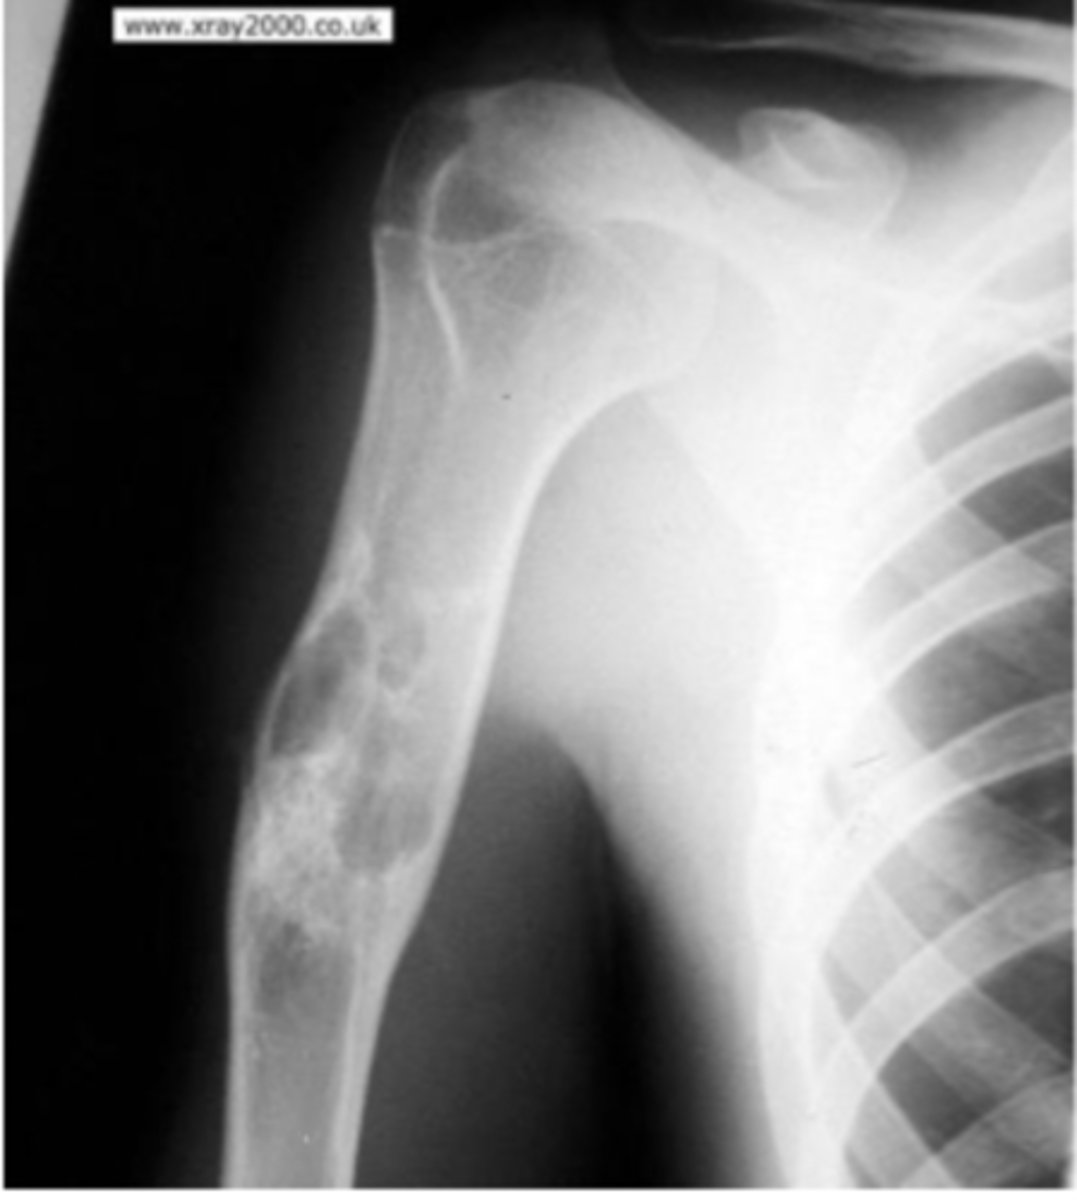

Fracture of the humerus and inferiorly displaced

What is the issue?

pathologic fracture

The sclerotic healing is likely caused by what prior implication?